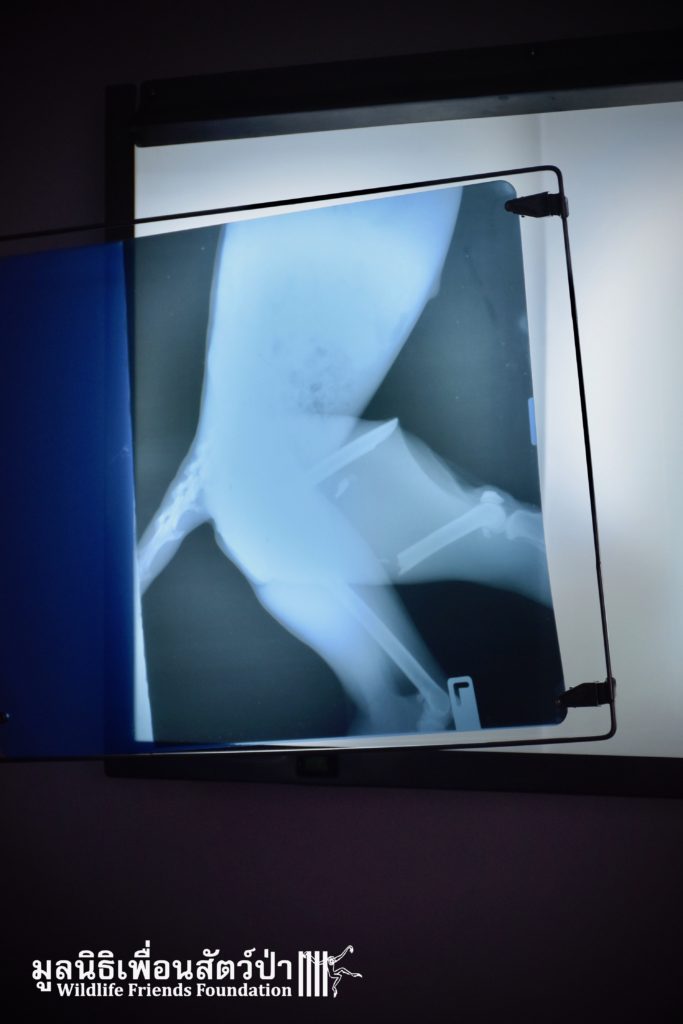

Open arrival to the scene the found a rather stressed langur with a very badly injured leg. The injured leg was visibly broken. To evaluate the situation further and access the damage the team took her to a local clinic to perform an x-ray, you can see the extent of the fracture from the images of the x-ray.

The team, planned to perform surgery the following day. The team agreed to try save the leg as without her leg a wild life would be difficult. The vet team inserted an intramedullary pin through the bones of her leg to re-joined the bones. So far the surgery seems a success, we will only be able to confirm this the coming days and weeks. We have named her ‘Rosy’. Rosy is currently recovering from her ordeal in the WFFT Wildlife Hospital in a small recovery enclosure to restrict her movement so her leg can have a chance to heal.